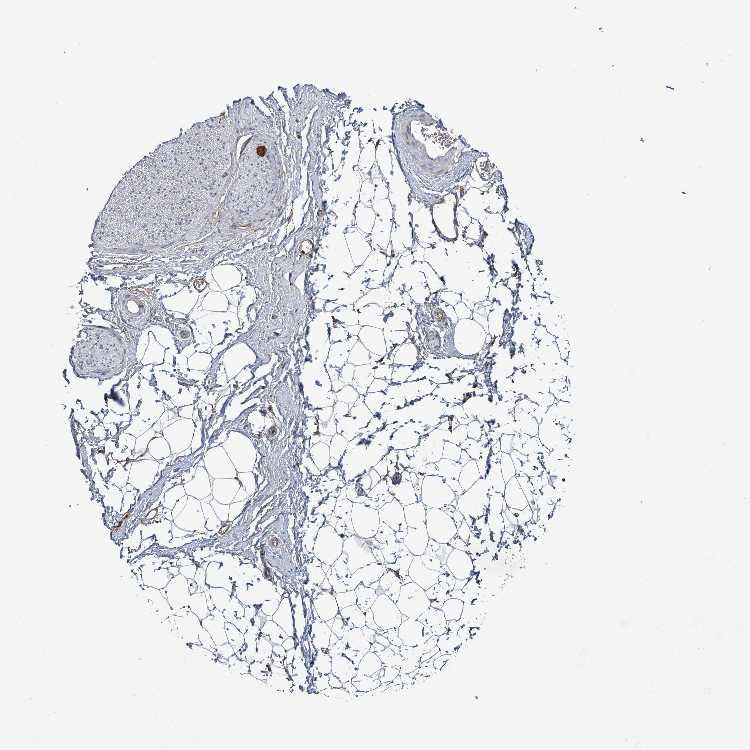

ADIPOSE TISSUE - Antibody stainingi

Antibody staining in the annotated cell types in the current human tissue is reported as not detected, low, medium, or high, based on conventional immunohistochemistry profiling in selected tissues. This score is based on the combination of the staining intensity and fraction of stained cells.

Each image is clickable and will lead to virtual microscopy that enables deeper exploration of all samples and also displays staining intensity scores, fraction scores and subcellular localization as well as patient and tissue information for each sample.

Antibody HPA050716

Adipocytes Not detected